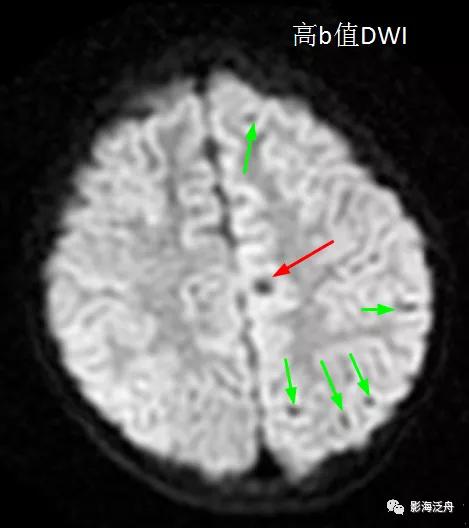

从理论上讲,无论高b值DWI还是低b值DWI序列都应该对磁敏感伪影很敏感,但实际情况是不是这样呢?看下图↓↓

上图可以发现,在低b值DWI序列上左侧额顶叶交界区的病灶显示清晰(红箭),但在高b值DWI序列上,除病灶外,多个脑沟也表现出磁敏感伪影(绿箭)。因此,当病灶足够小或者数量比较少的时候很难区分到底是伪影还是病灶,而低b值DWI序列可以较好地解决这一问题。

最后,是不是有了DWI就不需要做SWI序列了呢?显然不是,因为两者的成像机理差异很大,同时SWI序列还采用了完全流动补偿法以及三维成像技术,除大幅降低背景中的磁敏感伪影外,层厚还可以搞得非常薄,因此可以更加有效地检出微出血灶。